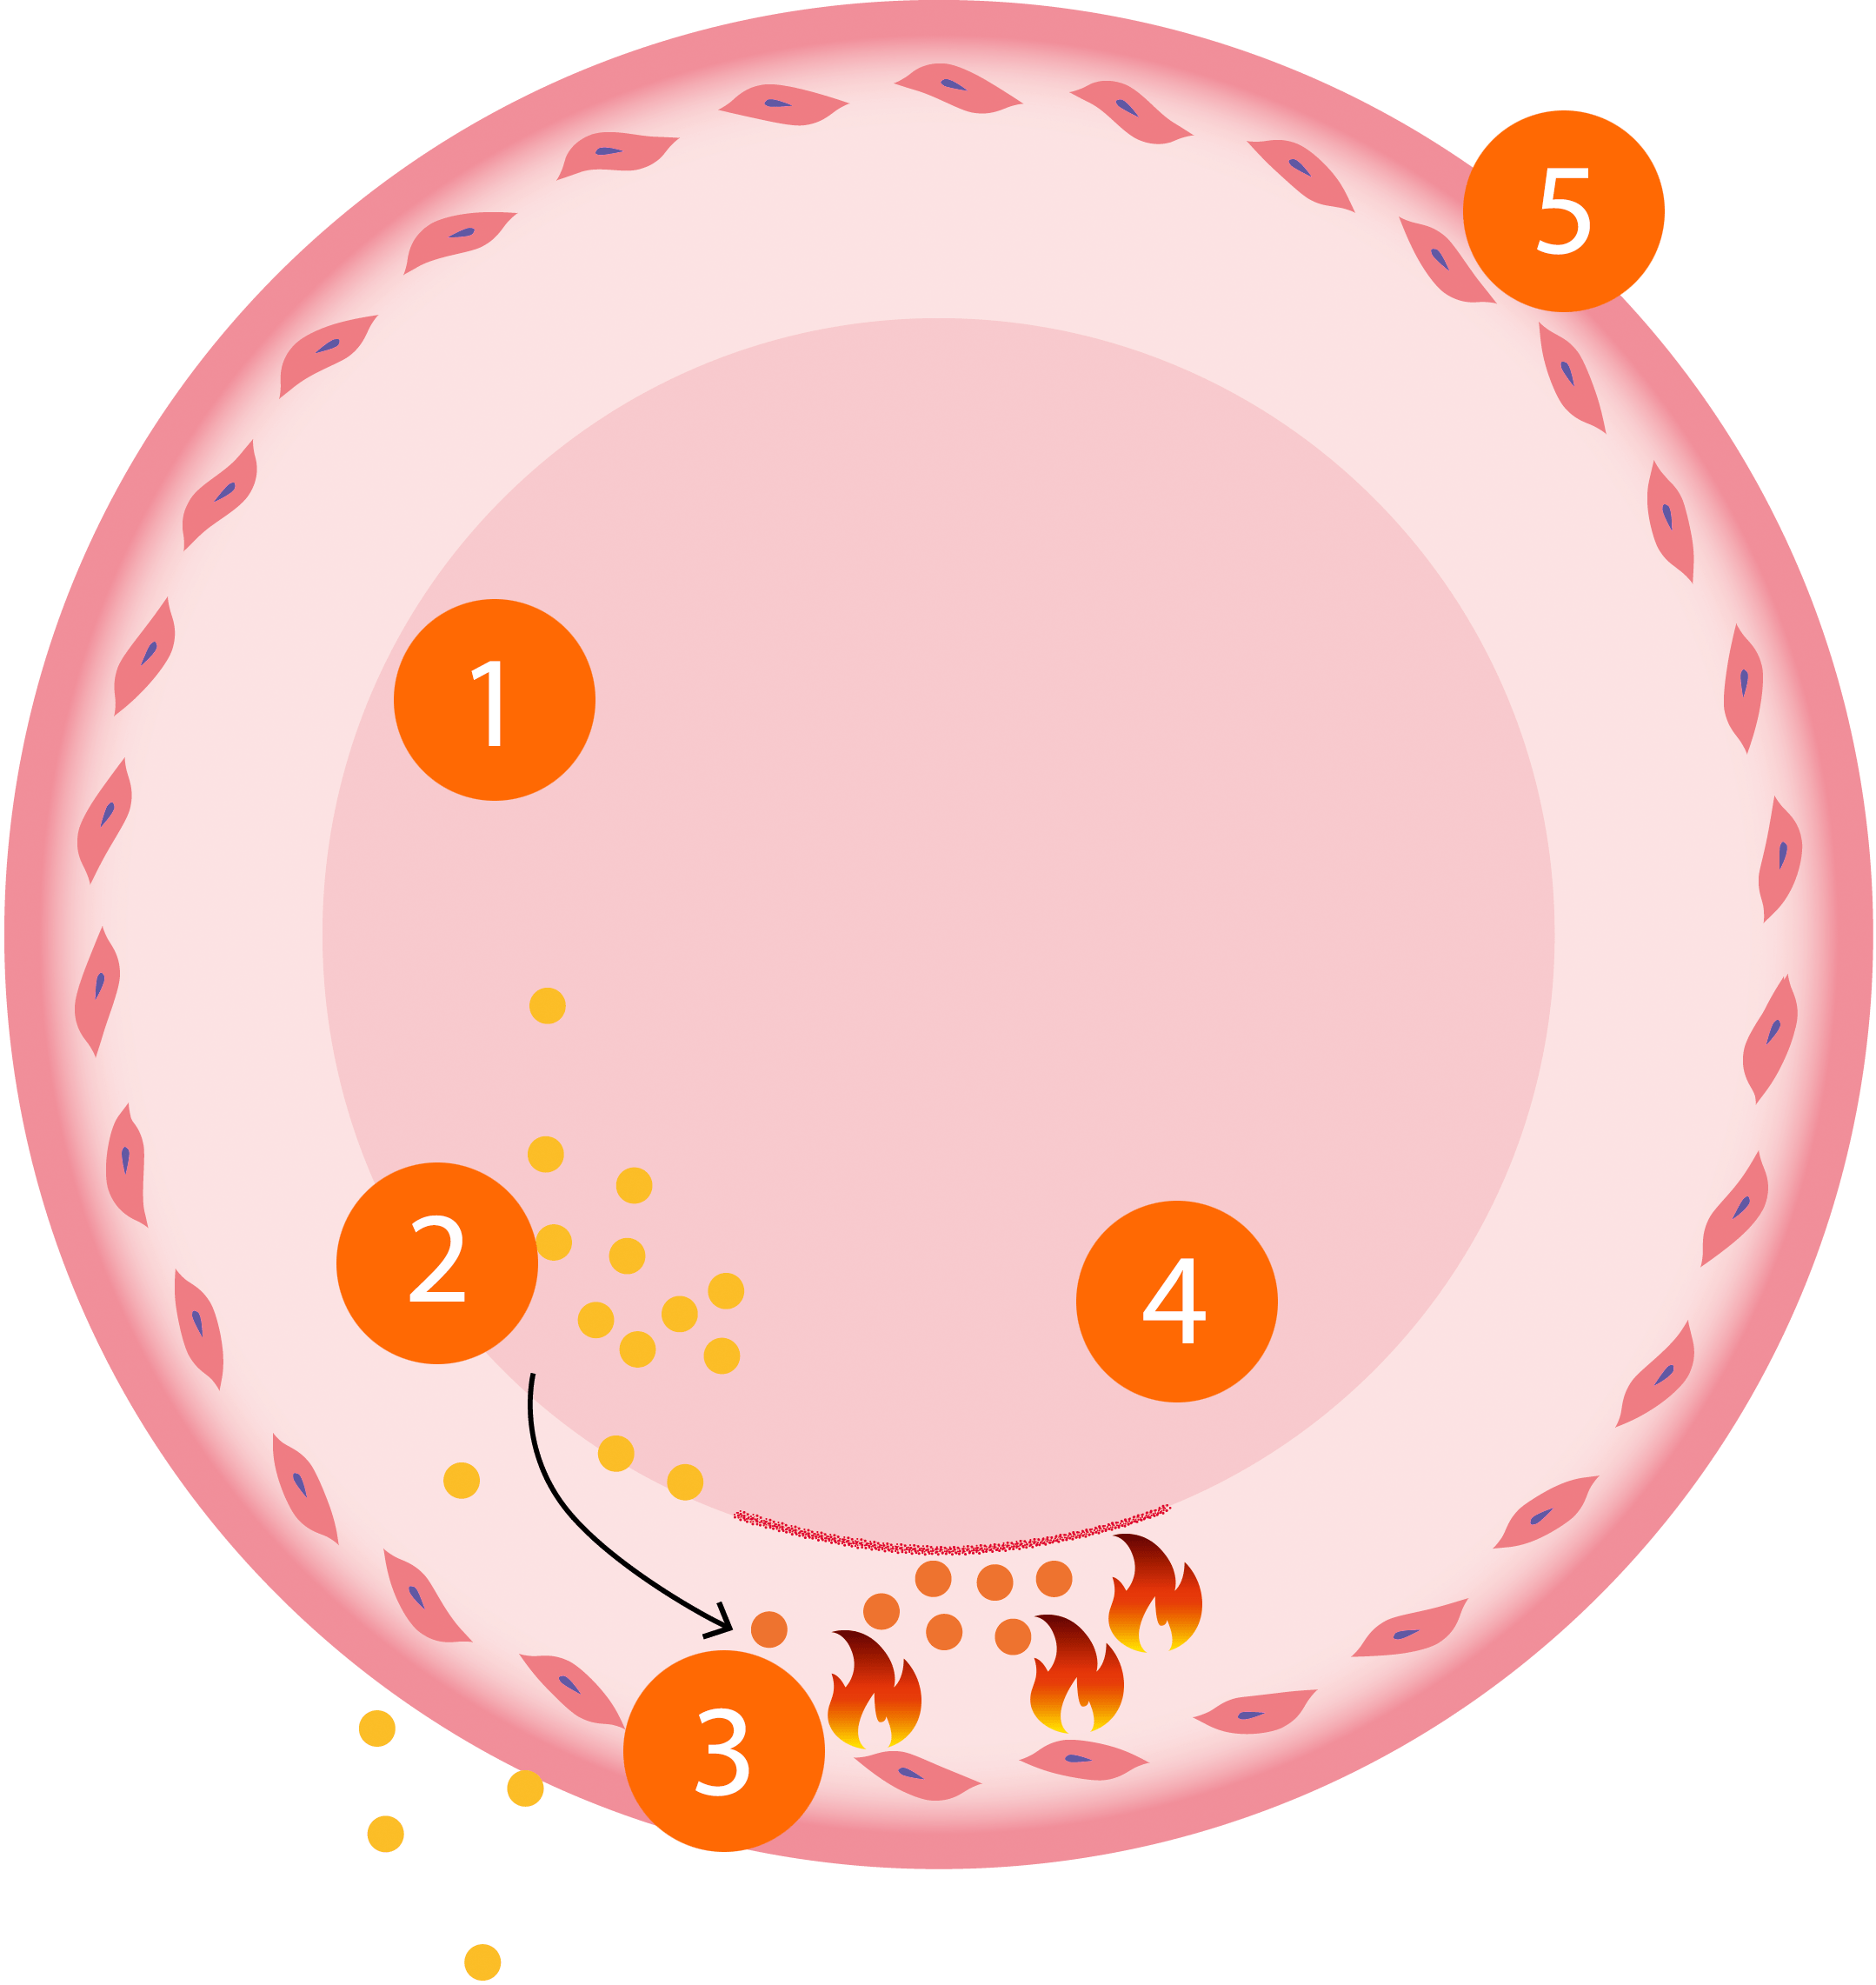

PADMA 28 active активний захист клітин

Поперечний переріз кровоносної судини

Патогенетичні та фізіологічні процеси у кровоносній судині

| 1. "Поганий" холестерин ЛПНЩ (жовтий). |

| 2. Вільні радикали (окислювальний стрес) сприяють утворенню окисленого холестерину ЛПНЩ. |

| 3. Окислений холестерин ЛПНЩ (помаранчевий) може вивести імунну систему з ладу. Якщо окислювальний стрес в організмі відбувається протягом тривалого часу, це може спричинити запалення ендотелію і, отже, призвести до поганого кровообігу. |

| 4. Клітинне харчування через кровоносні судини: нормальний кровоток забезпечує надходження поживних речовин до клітин за допомогою мікроциркуляції. |

| 5. Колаген підтримує кровоносні судини стабільними та еластичними. Волокна колагену складають «сито» у стінці судин, що є одним із бар'єрів проникнення з крові у тканини інфекцій та токсичних речовин. |